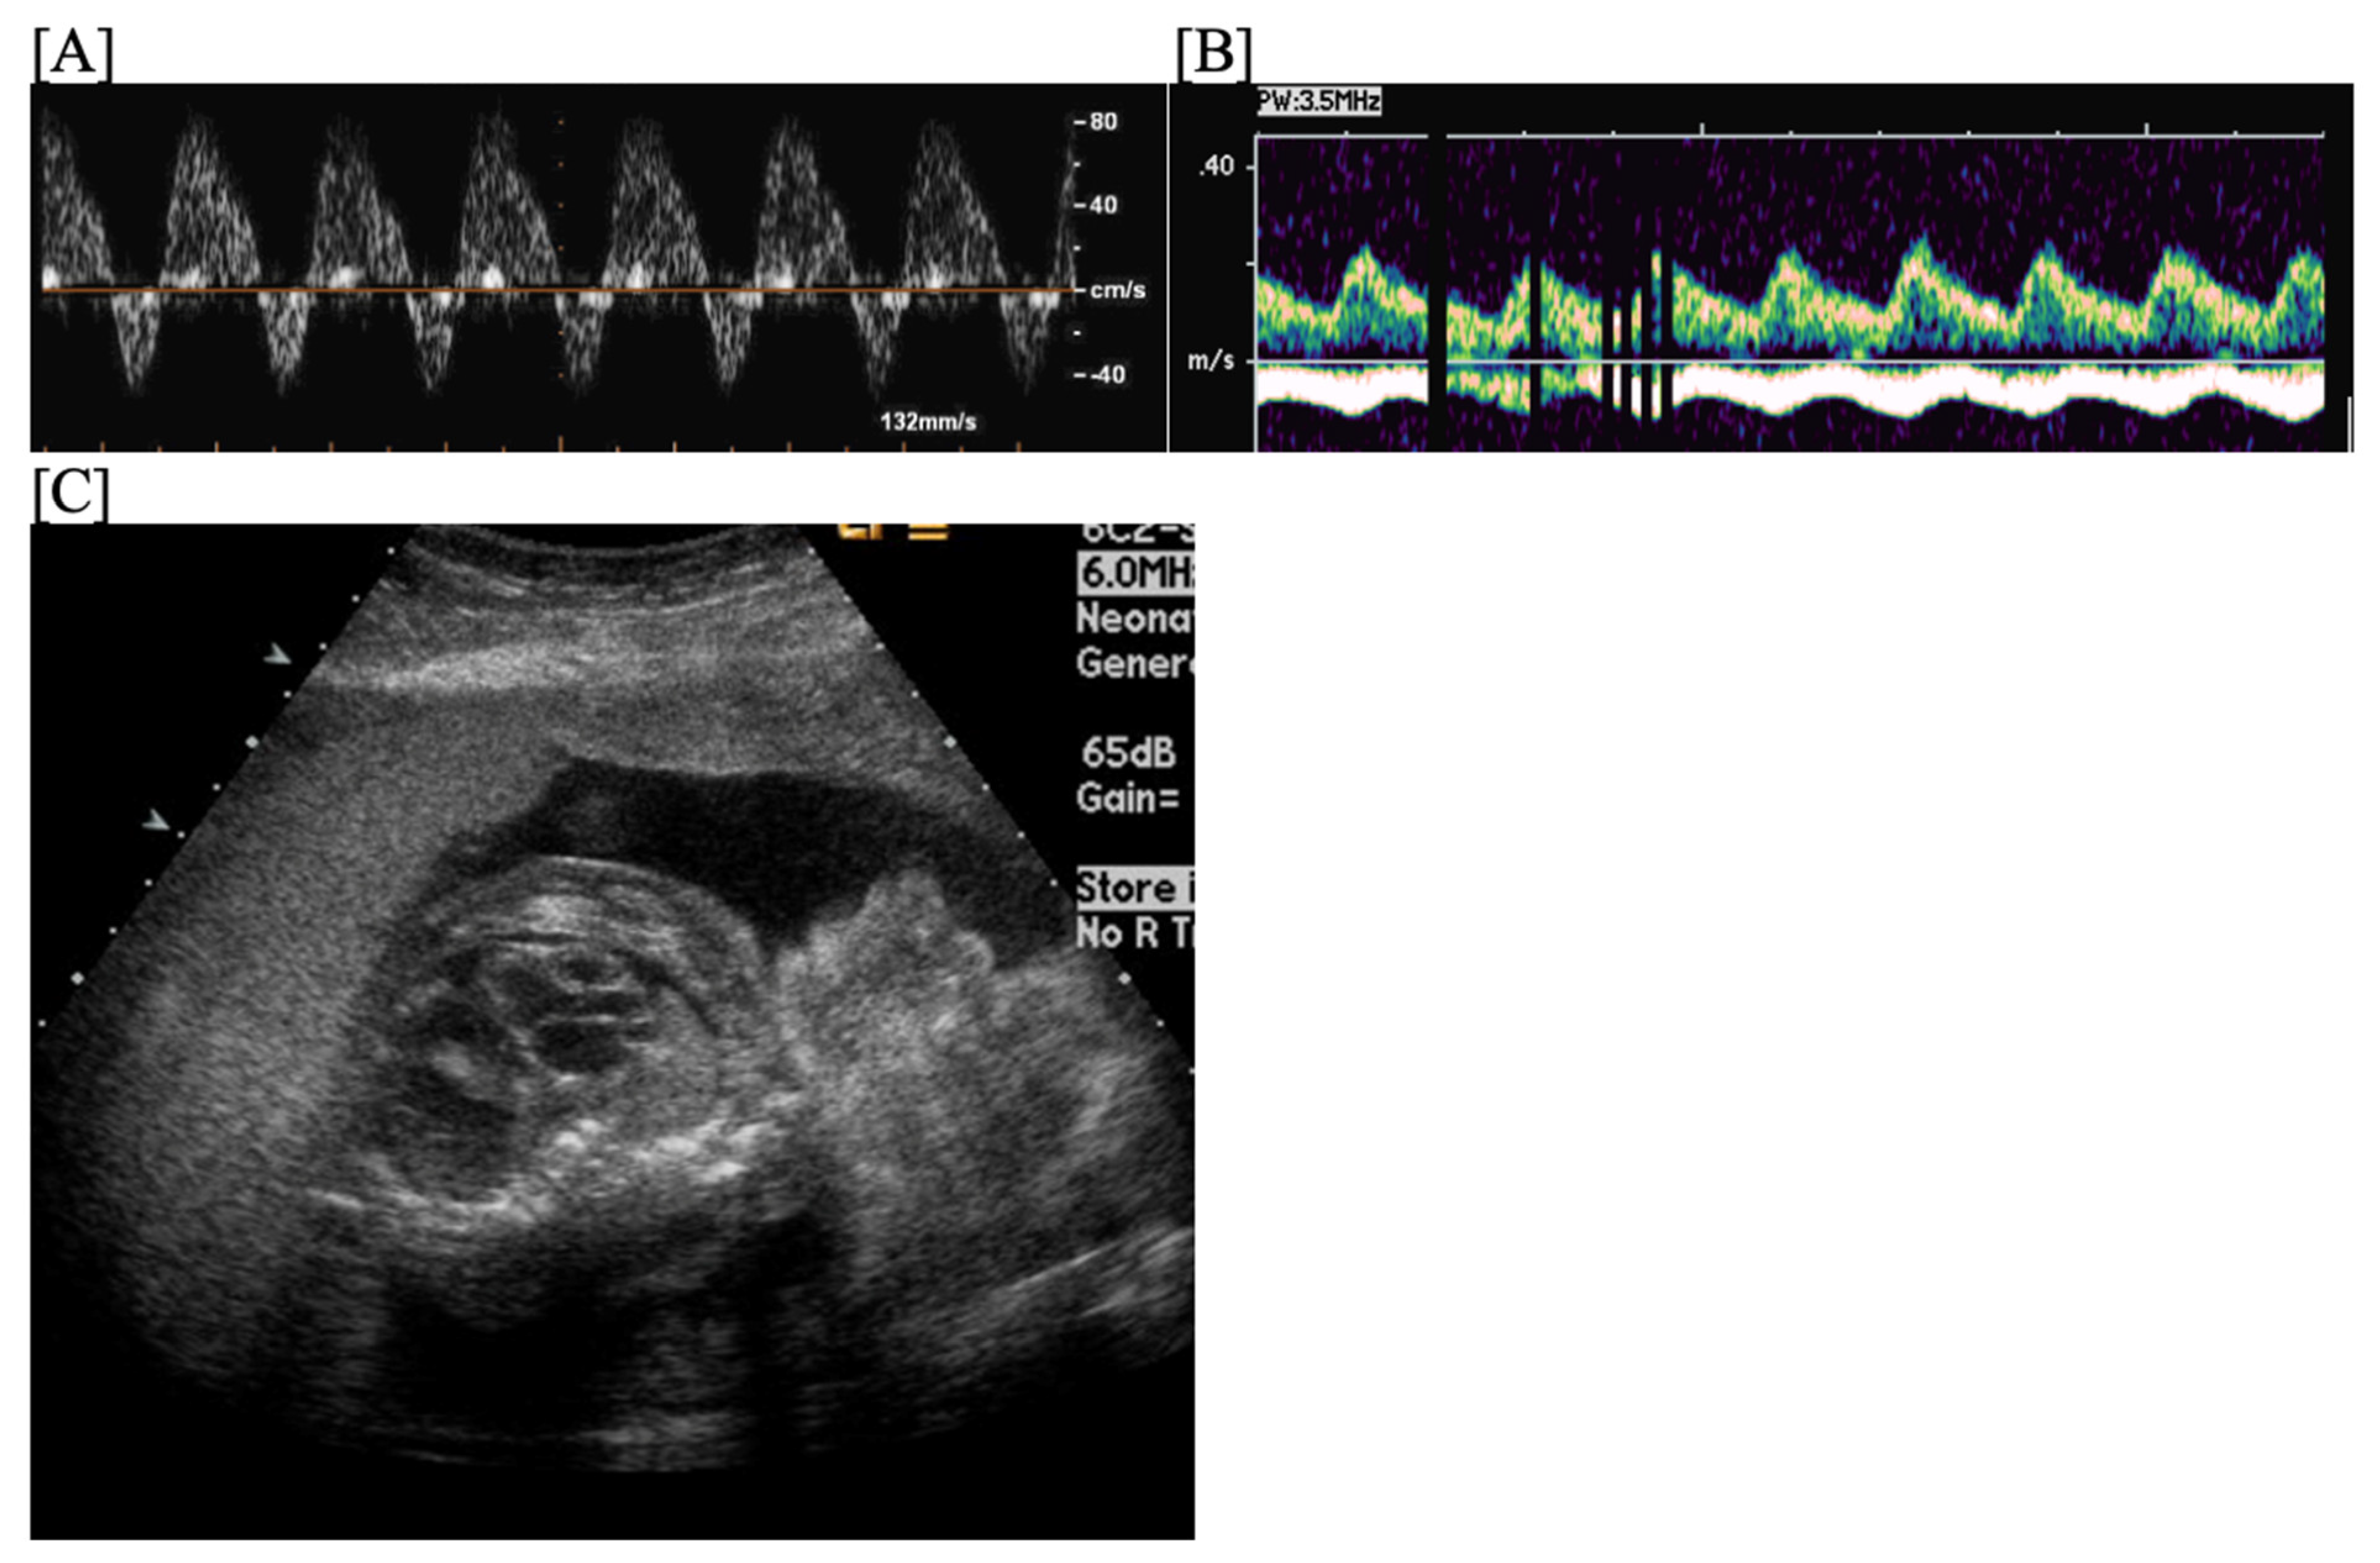

- Short VA SVT (Figure 3 and Figure 4) demonstrates a ventricular–atrial (VA) interval that is less than half of the ventricular–ventricular (VV) interval (VA:AV ratio < 1) and a sudden onset and termination of tachycardia; tachycardia usually terminates with a non-conducted atrial contraction. Short VA SVT includes AVRT (also known as orthodromic reciprocating tachycardia, ORT) and atrioventricular nodal reentrant tachycardia (AVNRT). Short VA SVT typically presents after 18 weeks of gestation.

- Long VA SVT (Figure 4) demonstrates a VA interval that is more than half of the VV interval (VA:AV ratio > 1). Long VA SVT includes EAT and PJRT. A distinguishing feature of EAT is tachycardia termination with ventricular contraction. Long VA SVT may occur as early as 12 weeks of gestation. Because long VA tachycardias have slower rates, they are less likely to cause hydrops.